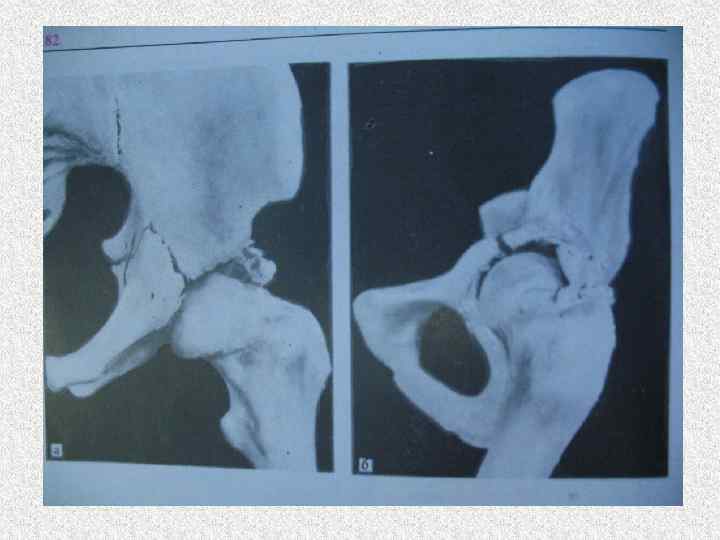

Повреждения водителя • Хлыстообразный перелом позвоночника в шейном отделе • Черепно-мозговая травма • Перелом грудины • Перелом бедра (диафиза, шейки) • Вывих тазобедренного сустава (Переломовывих) • Кровоподтеки, ссадины раны на выступающих частях тела • Ушибы сердца, легких, печени, селезенки. С разрывами или отрывами

Повреждения пассажира переднего сиденья • Хлыстообразный перелом позвоночника в шейном отделе • Черепно-мозговая травма • Перелом бедра (диафиза, шейки) • Вывих тазобедренного сустава (Переломовывих) • Кровоподтеки, ссадины раны на выступающих частях тела • Ушибы сердца, легких, печени, селезенки. С разрывами или отрывами